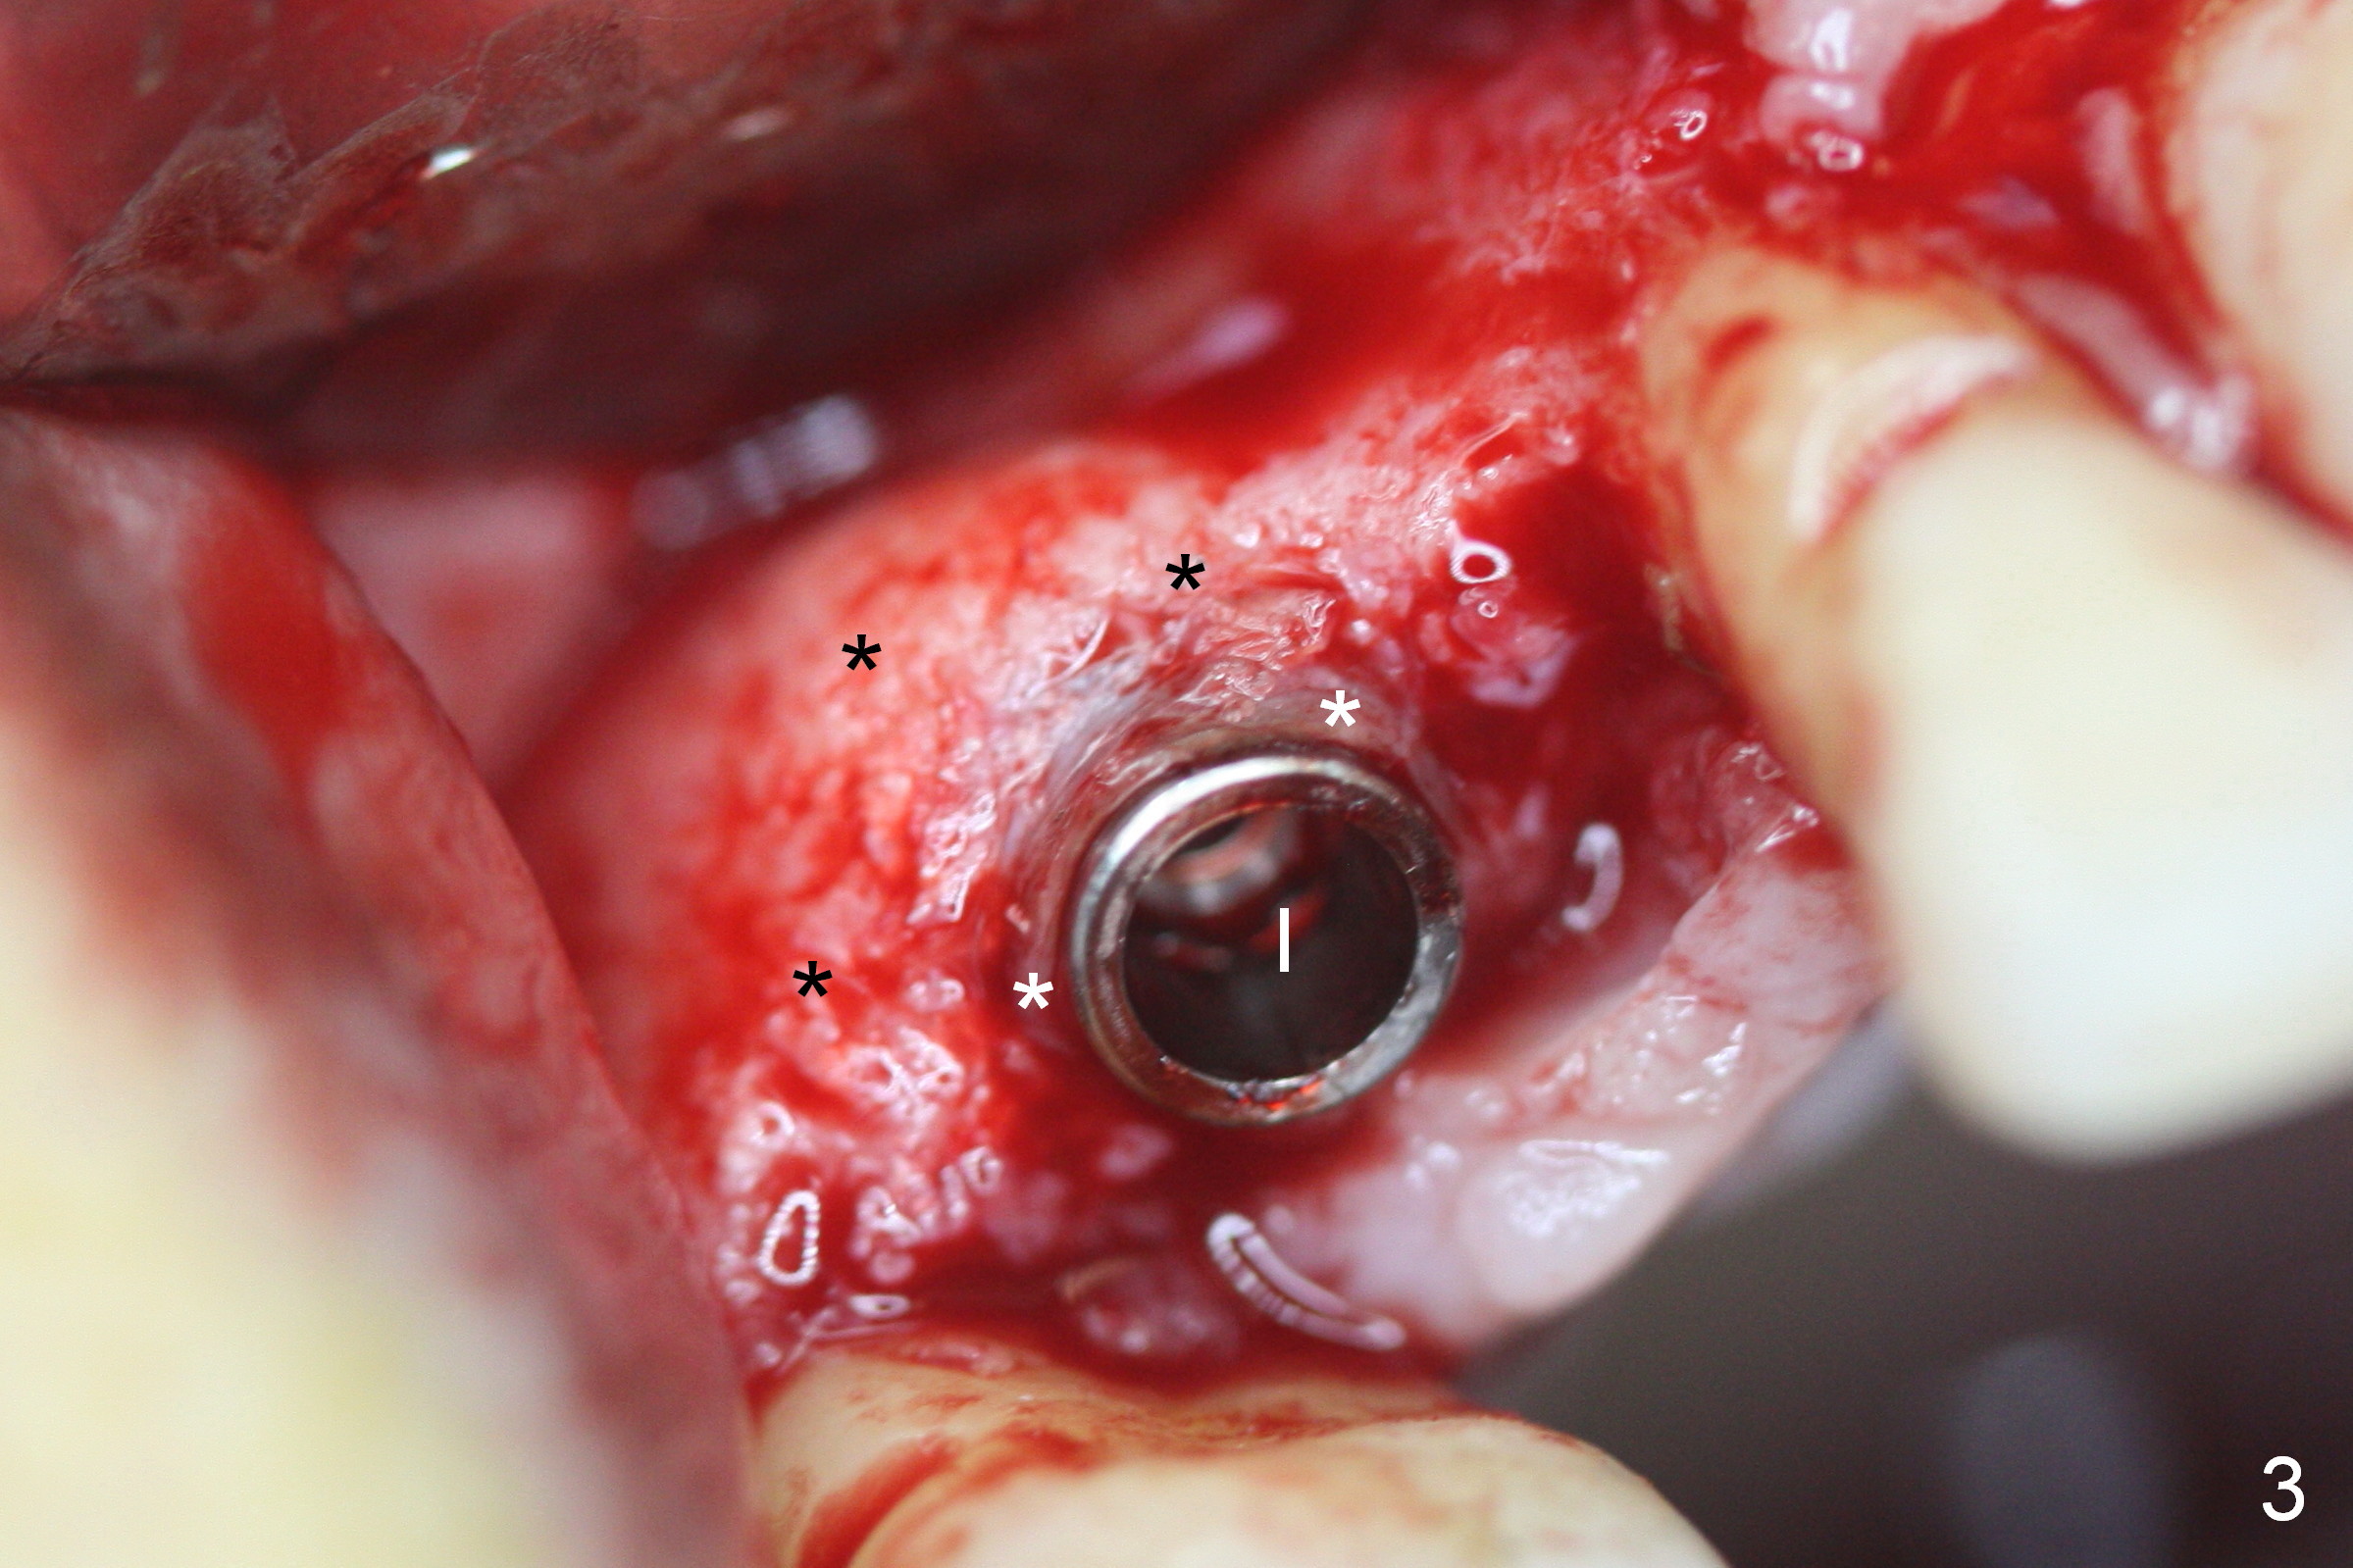

Four months post implant placement, the immediate provisional (Fig.1 P) has mobility with tenderness and perforation at the cervix (^). When the provisional is removed, the buccal plate bulging is more evident (Fig.2 arrowheads). The latter is apparently caused by bone expansion associated with implant placement (Fig.3 black *), since the bulging is not so obvious in a preop CBCT 3 D image (Fig.4 *). There is a layer of fiber granulation tissue (Fig.3 white *) around the mobile implant (I). More fiber tissue is noted when the implant is removed (Fig.5). A new osteotomy is created in the palatal wall of the existing implant site with 2 mm pilot drill, followed by 2.5 and 3 mm reamers. As a 4.5x17 mm tap is being inserted (Fig.6 T), it is deviated buccally. Reamers are re-used to try to remove more palatal bone to let the implant be placed more palatally. When a 4.5x17 mm tissue-level implant is placed (Fig.7,8 I with insertion torque >60 Ncm), there is a small buccal gap (Fig.8 *). A 20° angled abutment (Fig.7,8 A) is placed. An immediate provisional is fabricated with cosmetic satisfaction.